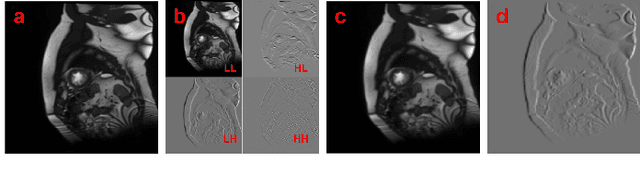

Abstract:Semi-supervised medical image segmentation (SSMIS) shows promise in reducing reliance on scarce labeled medical data. However, SSMIS field confronts challenges such as distribution mismatches between labeled and unlabeled data, artificial perturbations causing training biases, and inadequate use of raw image information, especially low-frequency (LF) and high-frequency (HF) components.To address these challenges, we propose a Wavelet Transform based Bidirectional Copy-Paste SSMIS framework, named WT-BCP, which improves upon the Mean Teacher approach. Our method enhances unlabeled data understanding by copying random crops between labeled and unlabeled images and employs WT to extract LF and HF details.We propose a multi-input and multi-output model named XNet-Plus, to receive the fused information after WT. Moreover, consistency training among multiple outputs helps to mitigate learning biases introduced by artificial perturbations. During consistency training, the mixed images resulting from WT are fed into both models, with the student model's output being supervised by pseudo-labels and ground-truth. Extensive experiments conducted on 2D and 3D datasets confirm the effectiveness of our model.Code: https://github.com/simzhangbest/WT-BCP.